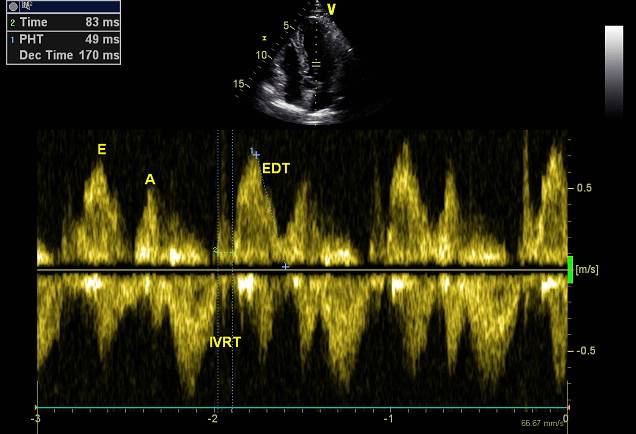

二尖瓣口流速与LA-LV压力阶差

◆E峰流速主要反映舒张早期LA-LV压力阶差,它同时受前负荷及LV松弛功能的影响。

◆A峰流速反映舒张晚期LA-LV压力阶差,它受LV顺应性及LA收缩功能的影响。

二尖瓣血流充盈模式

◆由E/A比值及DT决定的

◆正常、松弛功能障碍(I级)、LV假性正常化充盈(II级)及LV限制性充盈(III级)。

◆不典型的模式,如三相二尖瓣血流速度模式。